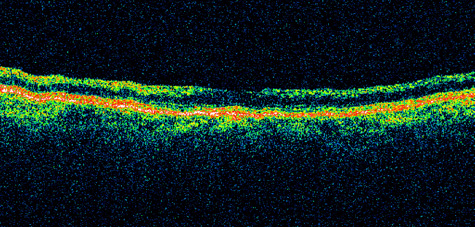

Hypoperfusion retinopathy is characterized by dot and blot hemorrhages in the midperiphery of the fundus, by venous tortuosity and engorgement, by microaneurysms, and by the occasional sludging of blood within the veins. Fluorescein angiography may show areas of capillary nonperfusion; it may also show microaneurysms in the midperiphery and slow arm to retina or arteriovenous transit time (Fig. 9A and 9B).174 The condition does not usually affect the posterior pole, and patients typically have normal visual acuity, although an occasional patient may have macular edema.174 The entire periphery of the eye is usually affected, although there may be more hemorrhages in one quadrant than another. Patients occasionally experience ocular discomfort or eye pain despite normal intraocular pressure. Reduction of the ophthalmic arterial pressure is a pathognomonic feature. Disc edema and disc collaterals are generally not present. The electroretinogram shows abnormalities in both the a- and b-waves (see Fig. 9C).

Fig. 9. Intravenous fluorescein angiogram of a patient with hypotensive or hypoperfusion retinopathy. A: There is a marked delay in the choroidal and retinal filling. B: In the recirculation of the angiogram, there is a characteristic staining of both arteries and veins. C: Electroretinogram shows normal a- and b-waves in the normal right eye (upper tracing) and marked redirection of the a- and b-waves in the affected left eye (lower tracing).